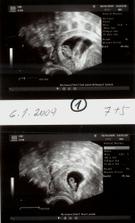

Vytoužené mimi . Vzhledem ke zdravotním problémům, operaci a věku mám za sebou IVF u Apolináře .Přes upozornění že napoprvé s tím raději nemáme počítat a šance že se uchytí obě není velká - čekáme dvojvaječná dvojčátka, která zatím ignorují tabulky a rostou stejně jako jedináčci. A vypadá to na kluka a holčičku. Děkuii všem u Apolináře a všem "snažilkám " za pomoc.